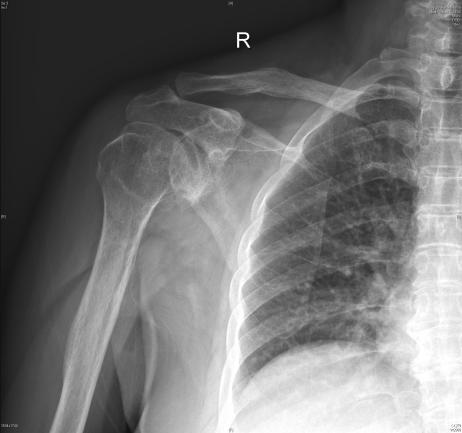

60岁的叶阿姨因反复右肩关节疼痛活动受限4年多,辗转就诊多家医院进行药物、物理治疗,但效果均欠佳,如今更是痛到连吃饭、穿衣服等日常动作都无法完成。经过四处打听后,叶阿姨慕名找到我院汤发强主任医师团队。

术前肩关节活动严重受限

汤发强主任医师为叶女士进行全面的身体检查,经过团队讨论及专业的分析,诊断为“肱骨头坏死伴右肩骨性关节炎”,决定为她进行反向肩关节置换手术

▲术前(左)术后(右)对比